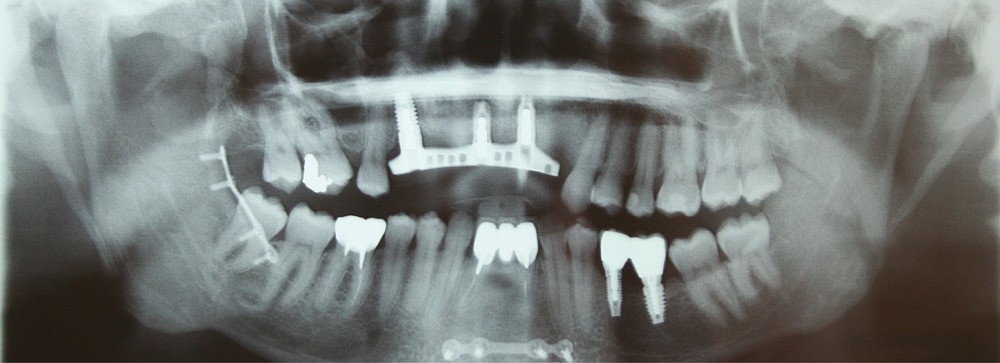

C’est la cause du traumatisme facial, souvent balistique par armes de guerre, qui distingue le patient militaire, candidat à une réhabilitation maxillo-faciale, du patient civil. Dans les conflits modernes, le visage des soldats reste exposé, mais les blessures imposant des reconstructions complexes comme des greffes fibulaires demeurent rares, limitant l’acte de réhabilitation à la réalisation de prothèses endo-orales étendues aux pertes de substance de l’os alvéolaire.